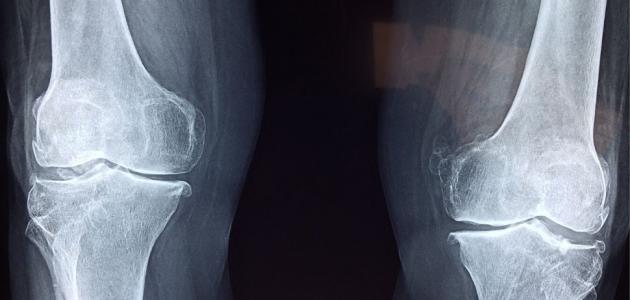

• الأشعة السينية: يتم من خلالها تحديد مكان حدوث التآكل في الغضاريف وتضييق مساحة المفصل والأماكن التي يتواجد فيها نتوءات، وهذا يساعد على استبعاد الأسباب الأخرى التي لم يكن هناك أي داعي لها.

يعرف احتكاك الركبة طبياً بالتهاب المفاصل والذي يكون عبارة عن حالة يتم فيها حدوث تلاشي للبطانة الطبيعية التي تتواجد بين المفاصل والتي تسمى بالغضاريف، وزوال تلك الغضاريف يتسبب في حدوث احتكاك لعظام المفاصل مع بعضها بشكل كبير وينتج عن ذلك آلام شديدة وتورم وتيبس وعدم القدرة على التحرك بشكل جيد.